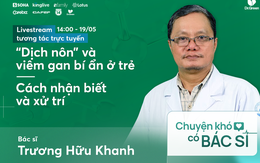

"Dịch nôn" và viêm gan bí ẩn ở trẻ khiến nhiều cha mẹ lo lắng: Cùng nghe phân tích từ BS

18/05/2022 12:15

Mời độc giả đón xem tọa đàm trực tuyến cùng với chuyên gia dịch tễ học, BS Trương Hữu Khanh, về chủ đề “Dịch nôn” và viêm gan bí ẩn ở trẻ: Cách nhận biết và xử trí.